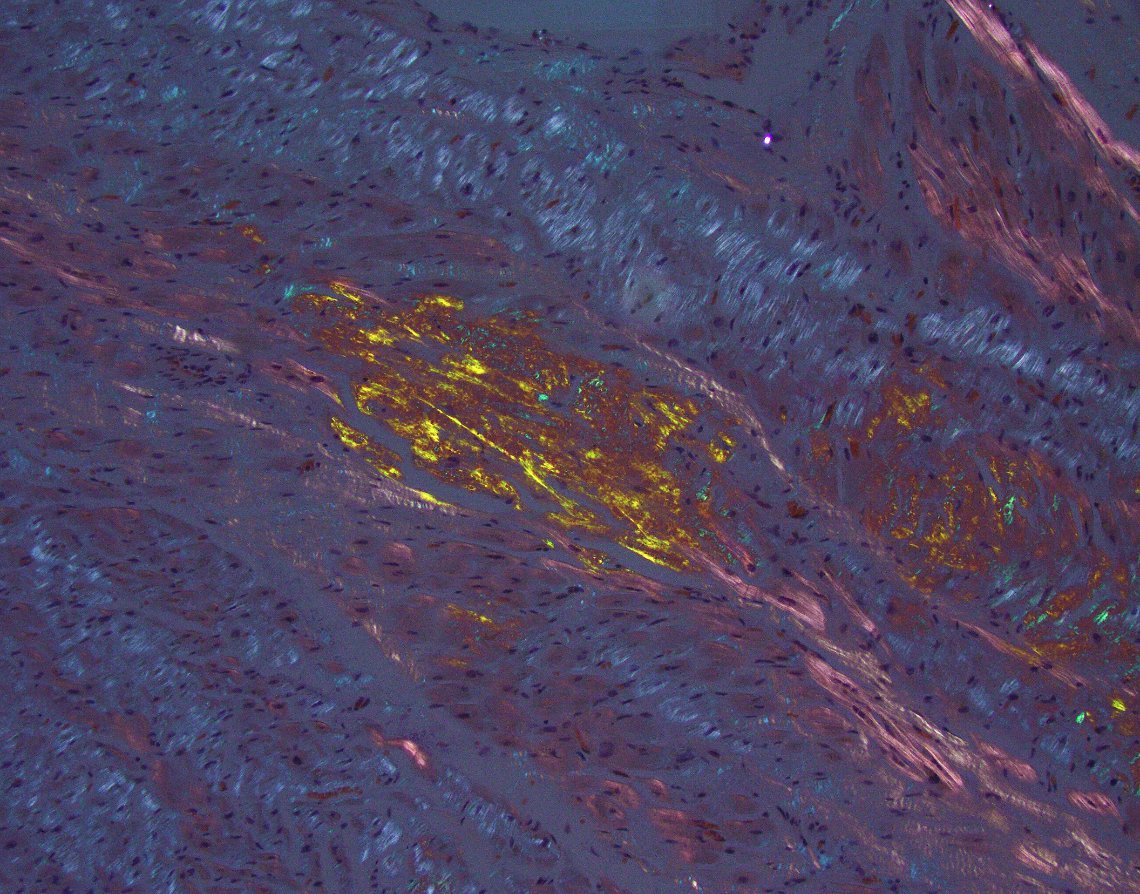

Surprising finding at autopsy (not an uncommon occurrence). Cardiac amyloidosis. Immediate cause of death in this case was aspiration pneumonia. Two reasons why it's good to have a polarizer handy when reviewing autospy slides. #cardiacpath